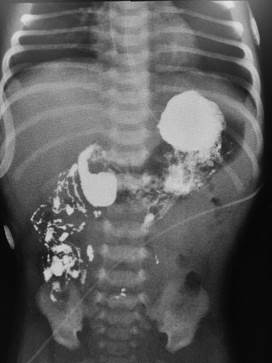

En la evolución el paciente se mantuvo estable, sin episodios de dolor ni distensión abdominal, y movilizando el intestino normalmente, pero al intentar retomar la alimentación enteral, se obtuvieron residuales biliosos altos, por lo que se decidió suspender, nuevamente, el aporte enteral, y solicitar un estudio radiológico contrastado de esófago-gastro-duodeno (Figura 3).

Figura 3: Estudio contrastado que muestra todo el intestino delgado a la derecha del abdomen con ausencia de llanta duodenal y ángulo duodeno-yeyunal, confirmando el diagnóstico de malrotación intestinal. Nótese el aspecto espiralado que adopta el contraste en el sector intestinal más proximal (insuficientemente jerarquizado durante la asistencia del paciente).

En el mismo no se observaron, ni la llanta duodenal y ni el ángulo duodeno-yeyunal, tal como se observa habitualmente a la izquierda de la columna. Por el contrario, el duodeno, el yeyuno y el resto del intestino delgado se encontraban a la derecha del abdomen, como ocurre en los pacientes malrotados.

El estudio por excelencia para el diagnóstico de la malrotación intestinal es el examen radiográfico contrastado del esófago-gastro-duodeno. En él se destaca la ausencia del arco duodenal característico, con el ángulo de Treitz a la izquierda de la columna, observándose en su lugar, como el contraste al salir del estómago se ubica rápidamente a la derecha de la columna, como vimos en el segundo paciente. Igualmente debemos recordar que, si bien menos frecuente, existen pacientes que presentan una rotación normal del duodeno, pero con una falta de rotación del colon, que también los pone en riesgo de sufrir un vólvulo del intestino medio.

En los casos en que la malrotación asocia un vólvulo de intestino medio, esta descripta la imagen en tirabuzón en las tomas de perfil, que corresponden al sector volvulado. Destacamos que, en el estudio contrastado de nuestro segundo paciente, se observa un aspecto espiralado del sector más proximal de intestino, que debió conducir al planteo de vólvulo y que fue pasado por alto.

A pesar de ser este, de los casos presentados, el que tuvo la mejor evolución, analizado en este momento vemos que la interpretación de este estudio fue insuficiente. Es una enseñanza para futuros casos, la importancia que se debe dar a una imagen de este tipo. Aún en ausencia de elementos clínicos que sugieran isquemia intestinal, esta imagen debe hacer plantear la posibilidad de vólvulo y debe llevar a una cirugía de urgencia a continuación de su identificación y el vaciado del estómago mediante la aspiración por sonda nasogástrica.